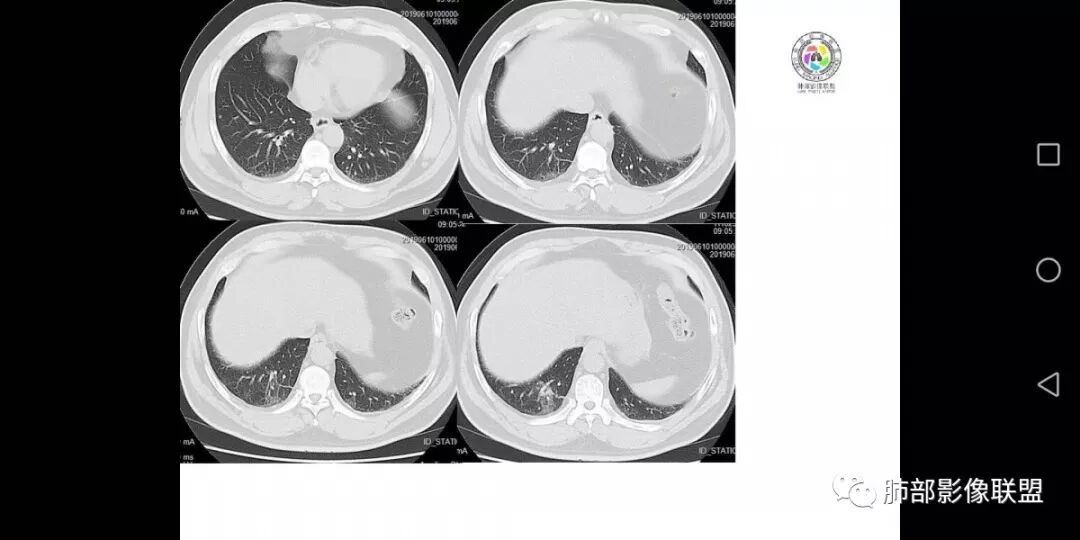

患者男,45岁,因乏力、低热、心悸入院,最高体温38℃,偶有咳嗽、无咳痰、咯血,肿瘤标志物阴性。

影像资料

男,45岁;乏力、低热、心悸,38°,偶咳;症状像结核,但无钙化,无积液;三期:35-57-71偏心空洞,冠状位胸膜有牵拉力:需考虑鳞癌,男性,45岁,年龄偏小,吸烟史?